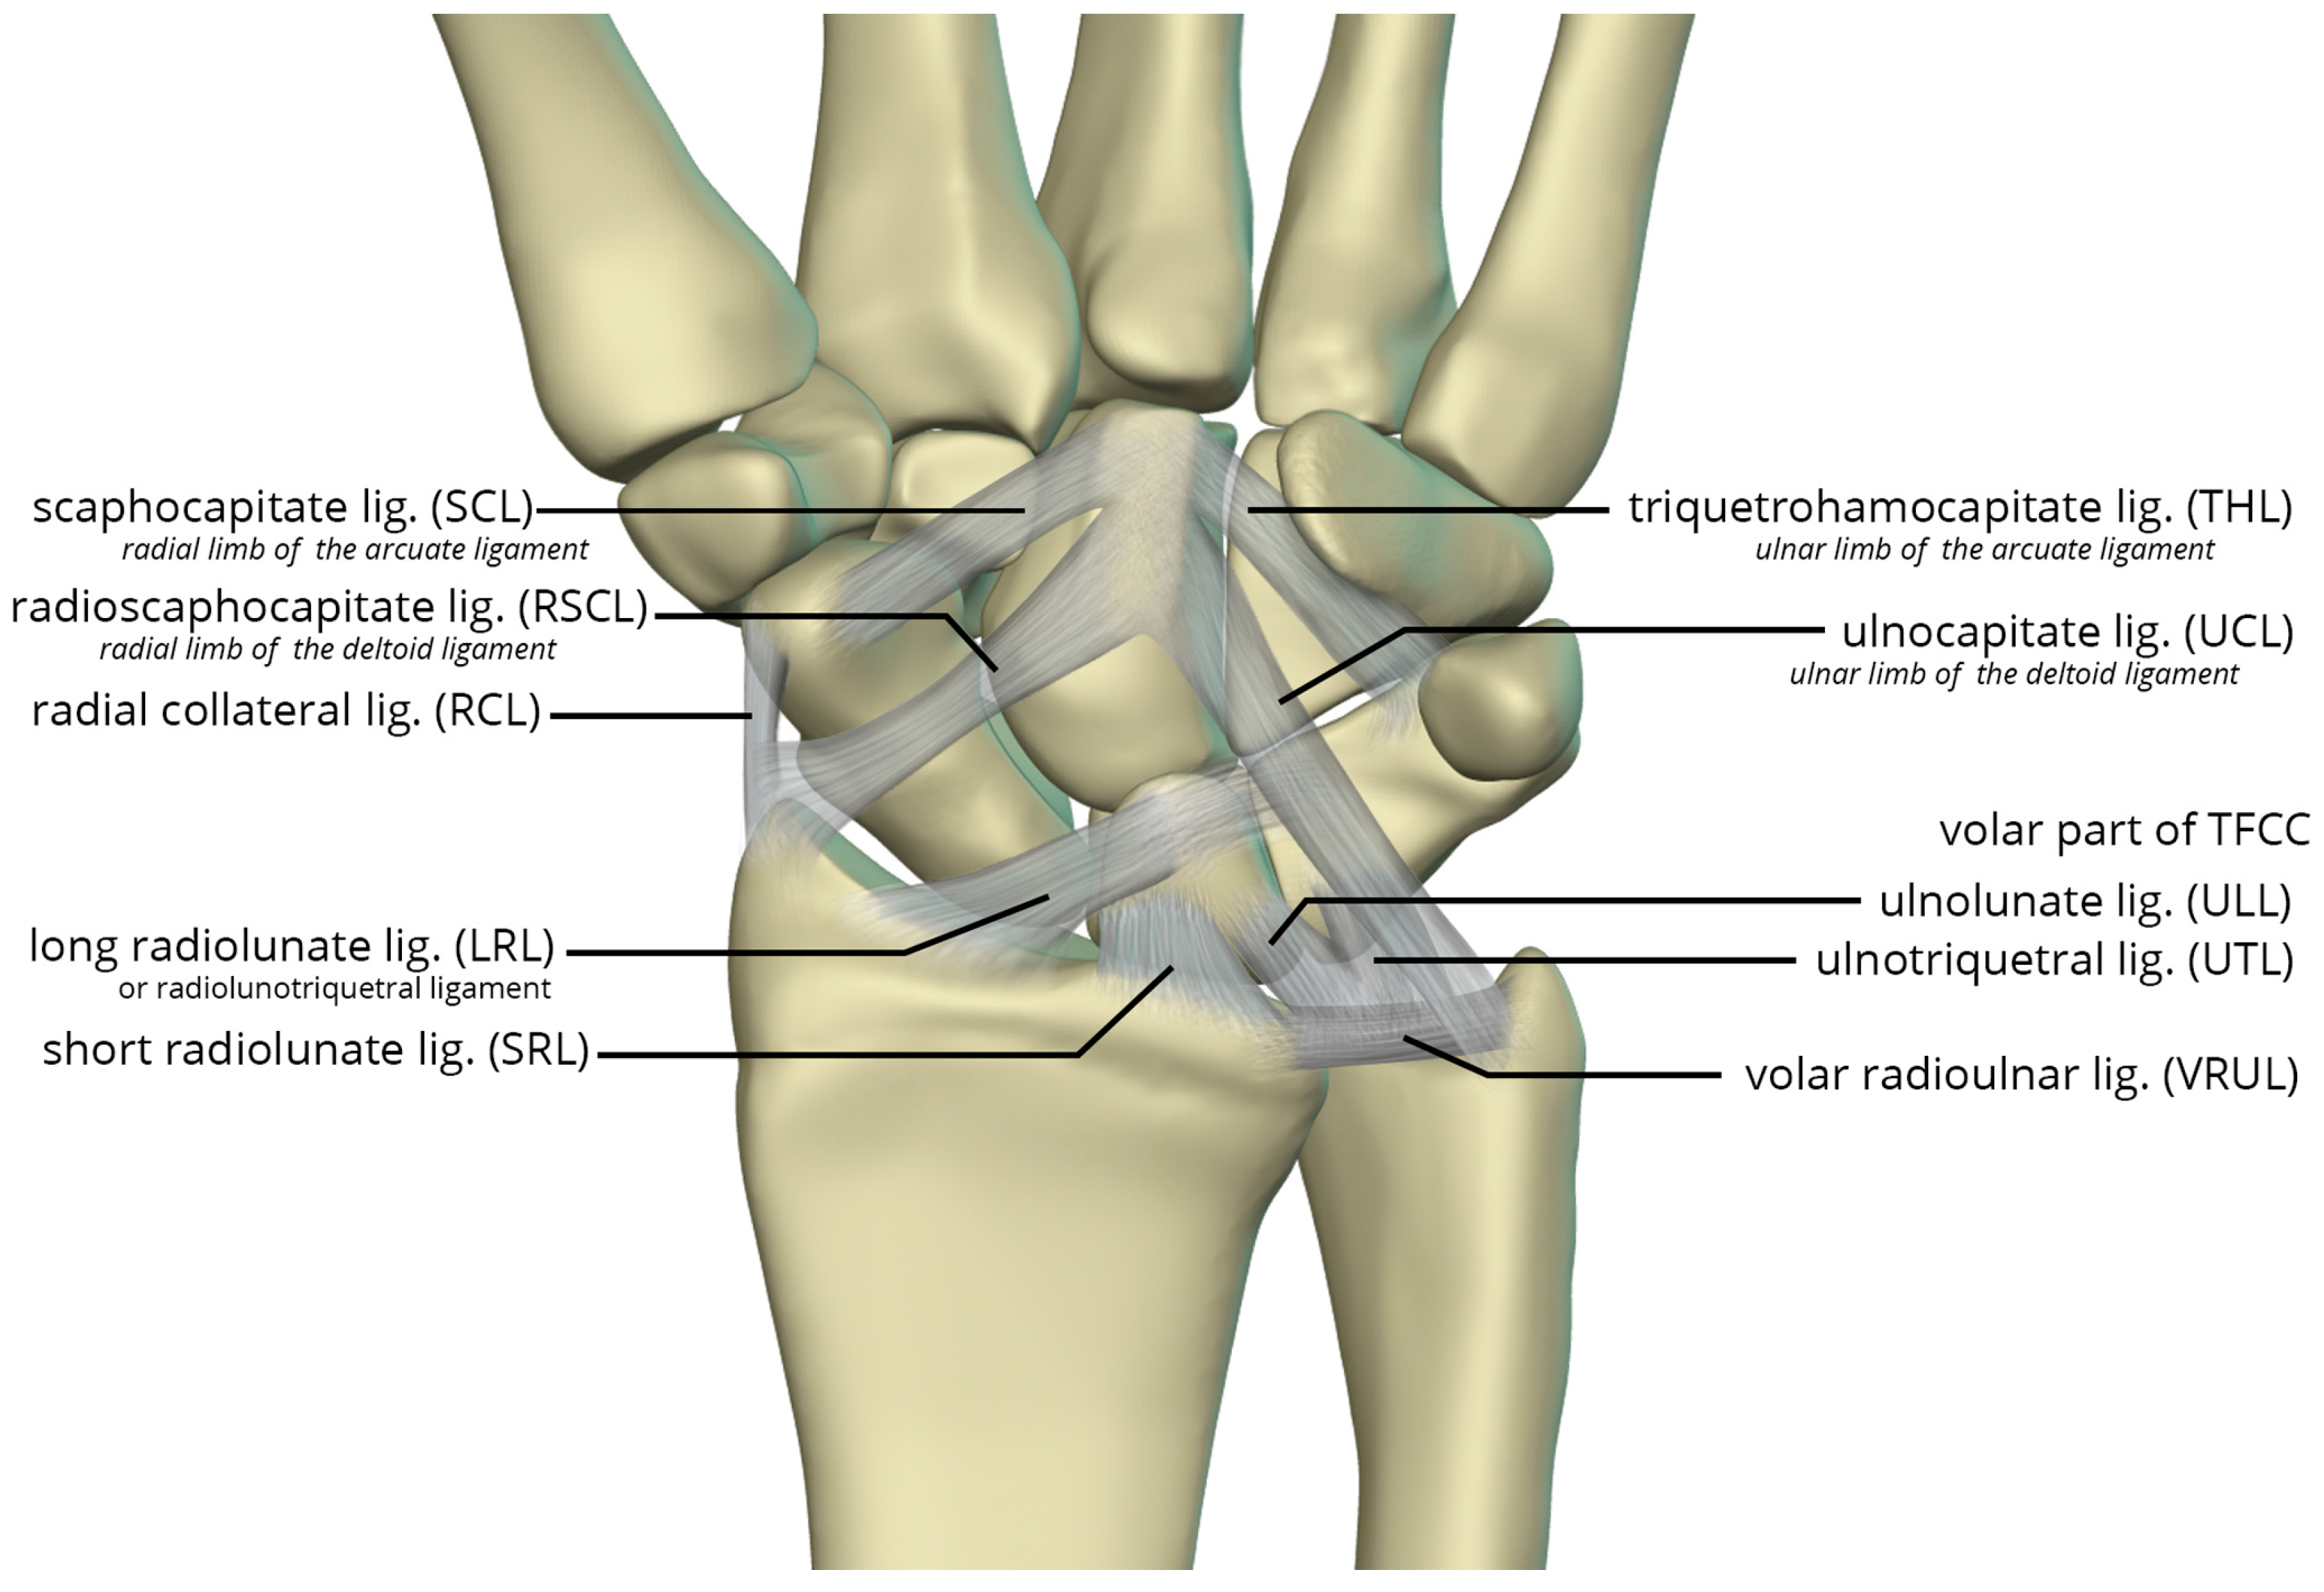

The volar radiocarpal ligaments include the radial collateral ligament (RCL), radioscaphocapitate ligament (RSCL), short radiolunate ligament (SRL), and long radiolunate ligament (LRL) (Figure 26). . The RCL extends from the radial styloid to the scaphoid head. The RSCL arises from the radial half of the volar rim of the scaphoid fossa. The RSCL attaches to the capitate, forming a sling across the scaphoid. Some fibers may attach to the scaphoid. The SRL anchors the lunate from the radial half of the volar cortex of the lunate to the volar rim of the lunate fossa of the radius. The LRL arises from the volar aspect of the ulnar half of the scaphoid fossa rim of the radius. Distally, the LRL attaches to the volar aspect of the lunate, with some fibers also attaching to the volar triquetrum, and therefore may also be known as the radiolunotriquetral ligament.

The volar ulnocarpal ligaments (Figure 26) include the ulnolunate ligament (ULL), the ulnotriquetral ligament (UTL), and the ulnocapitate ligament (UCL) [23,24]. The ULL and UTL originate from the volar radiolunate ligament and attach distally to the volar surfaces of the lunate and the triquetrum, respectively. The UCL extends from the ulnar head to the capitate. The ULL and UTL, deeper to the UCL, is a single sheet of tissue arbitrarily divided according to their distal attachments.

Lastly, the volar midcarpal ligaments include the arcuate and deltoid ligaments that are further subdivided into radial and ulnar limbs. The scaphocapitate ligament (SCL) arises from the ulnar aspect of the distal pole of the scaphoid, deep to the RSCL, and extends to the volar capitate body. It represents the radial limb of the arcuate ligament. The triquetrohamocapitate ligament (THL) extends from the triquetrum to the capitate, across the hamate. It represents the ulnar limb of the arcuate ligament. Some describe this as the distal band of the palmar scaphotriquetral ligament, which is another mid-carpal capsular ligament superficial to the SCL and THL [24,25]. The distal RSCL represents the radial limb of the deltoid ligament and the UCL constitutes the ulnar limb of the deltoid ligament, supporting the head of the capitate [25].

Figure 26. Illustration of the volar extrinsic carpal ligaments including the volar midcarpal ligaments, volar capsular ligaments, and volar ulnocarpal ligaments.